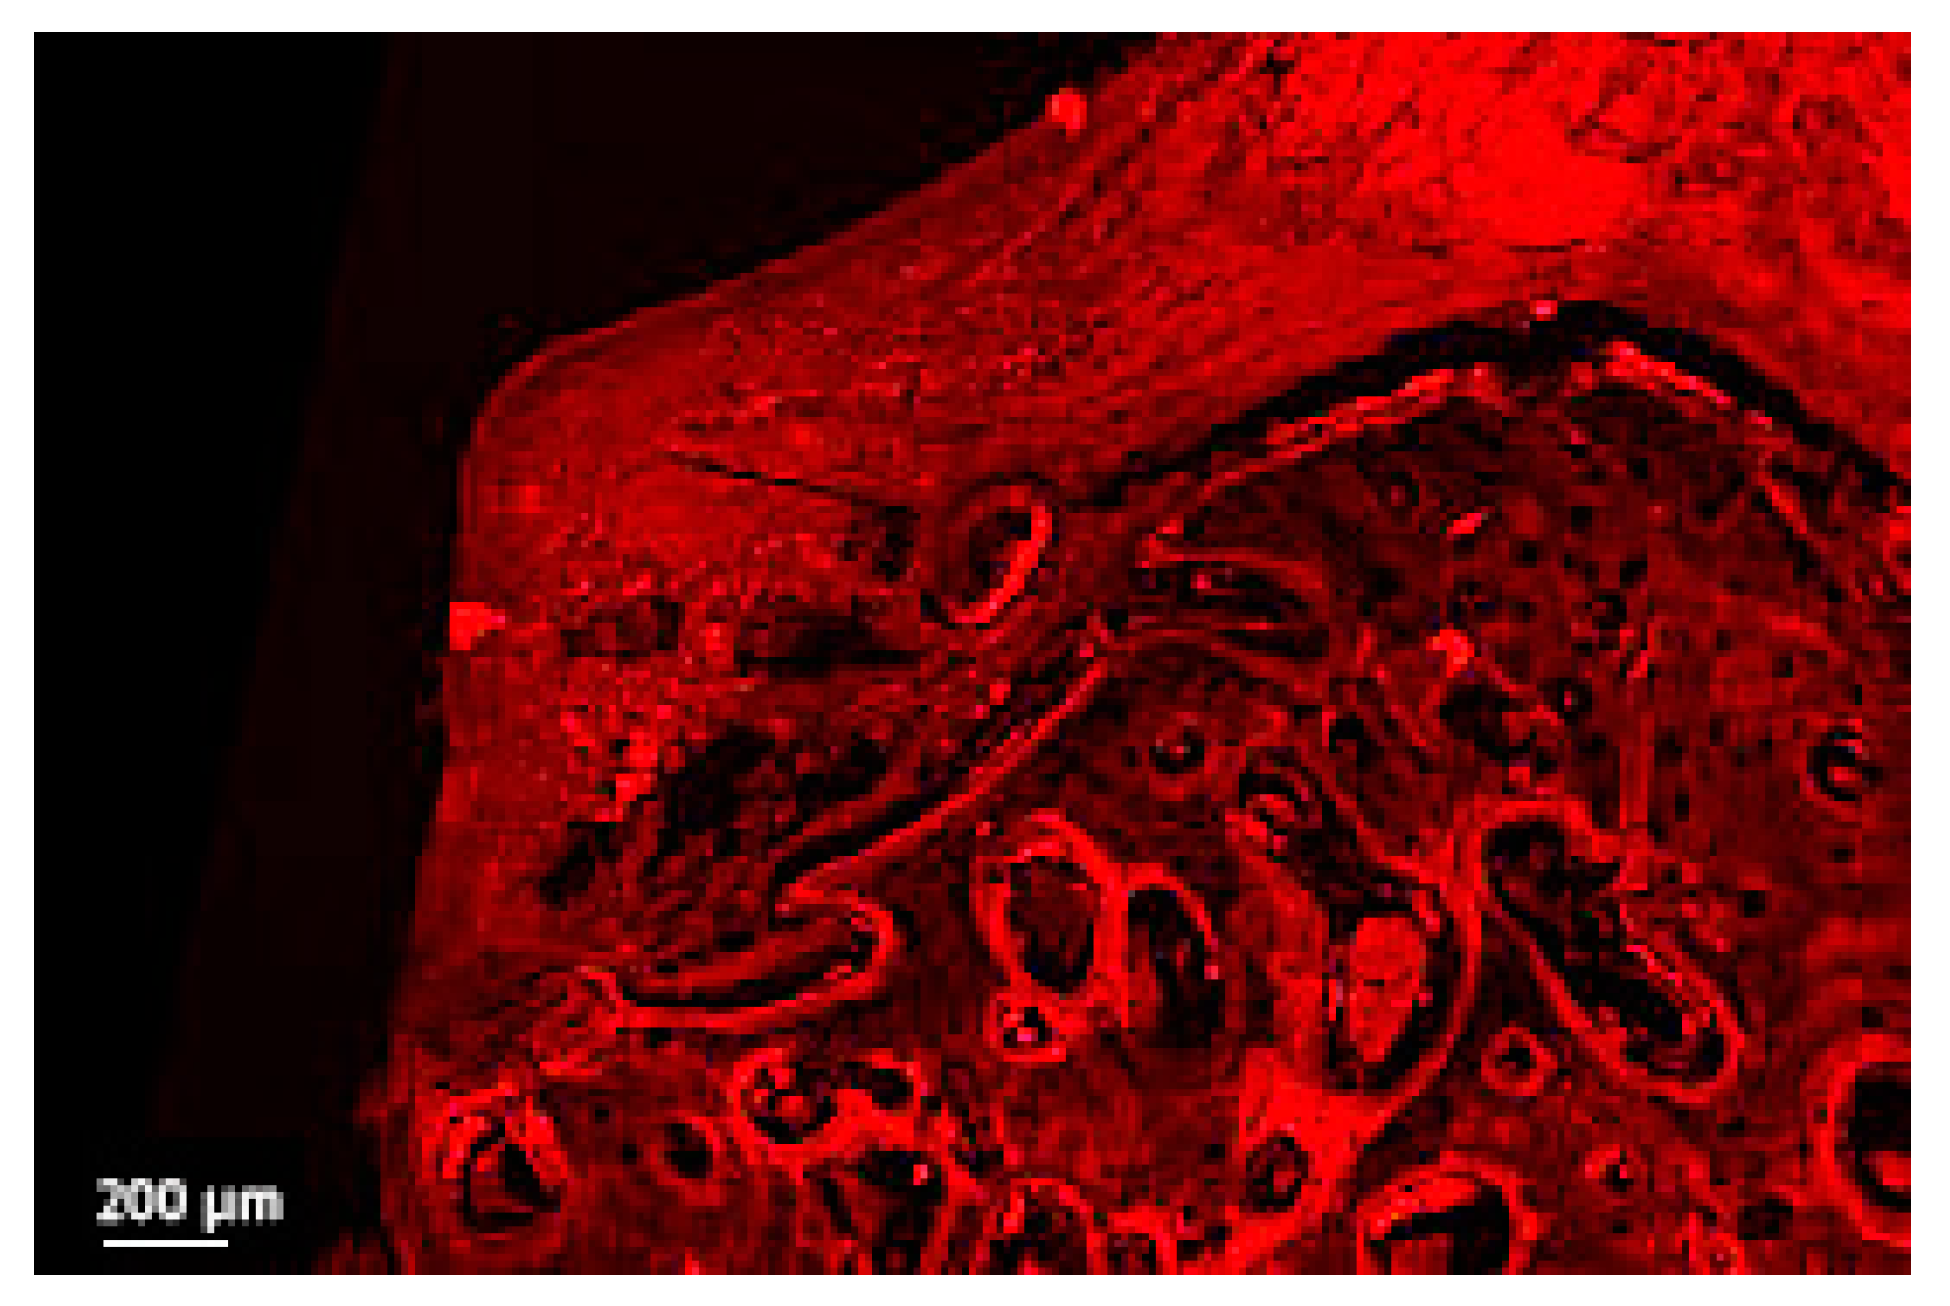

Figure 6.

Detail of the soft tissue bone in a thick section of a non-ligated implant. Note the ulcerated buccal pocket epithelium, the interrupted epithelial lining, the infiltration of inflammatory cells and the disruption of collagen network (implant #2, oral aspect; bar, 200 µm).